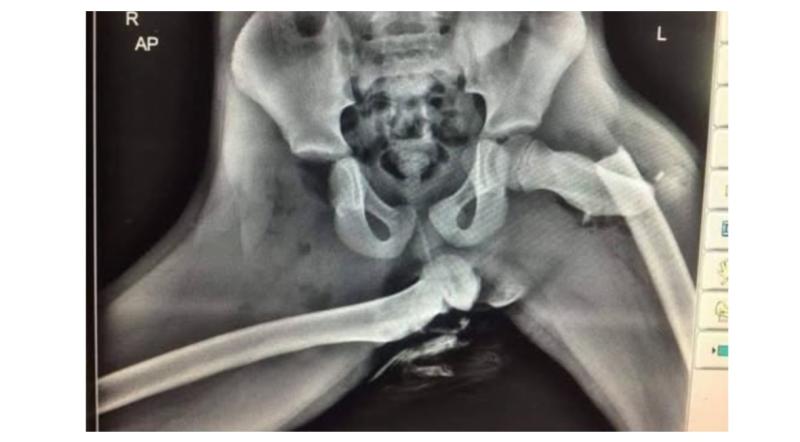

Gardaí urge passengers not to sit this way with an image of an Xray of a passenger in aftermath of a crash

In a post shared to social media, Kilkenny gardaí showed an image shared with them by a Welsh police officer involved in casualty reduction, they said: "It's not a new image but never gets old. It's an Xray of a passenger in a car that had her feet up on the dashboard when a collision occurred."

They continued: "When a collision occurs, it's not the speed does the damage but slowing down. For safety systems to function properly in modern cars, you need to be seated correctly with your approved restraint functioning properly.

"You need to have your seatbelt on correctly, the seat angled correctly, your feet where they should be and all your passengers likewise."

The post concluded: "Save our Paramedics and Medical personnel from seeing sights like this. Save yourself from suffering them."